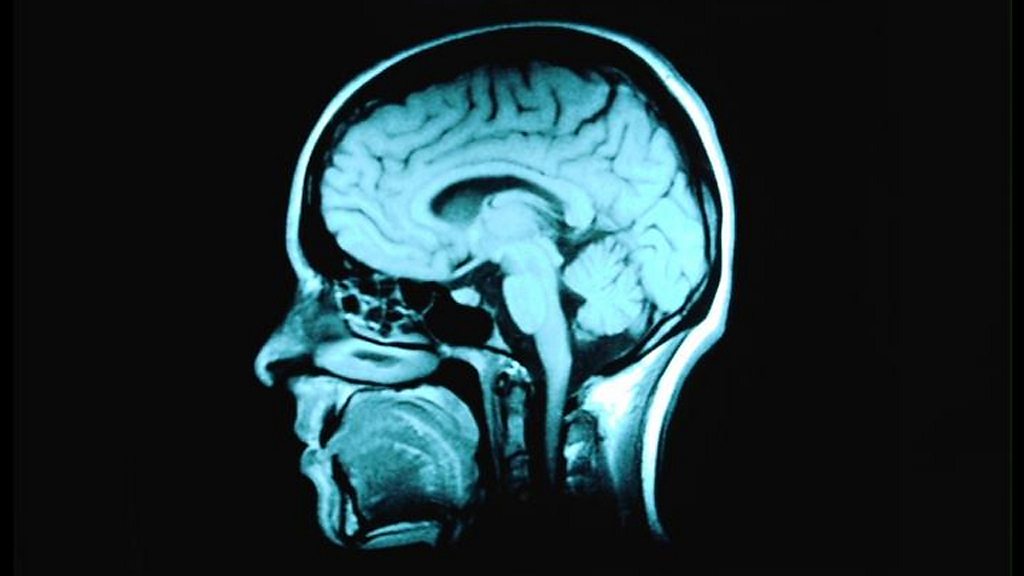

Geoff Watts meets researchers trying to find a new way to fight depression by studying those who never get it. In the second of two programmes Geoff meets scientists at the University of Manchester, studying the brains of people who have undergone traumatic life events without becoming seriously depressed and comparing them to the brains of those people who do. The hope is that new psychological therapies or even preventative medications might be developed to treat the one in five people who will at some point in their lives, become clinically depressed. (Image: MRI scan of the head and brain. Credit: Corbis Royalty Free)